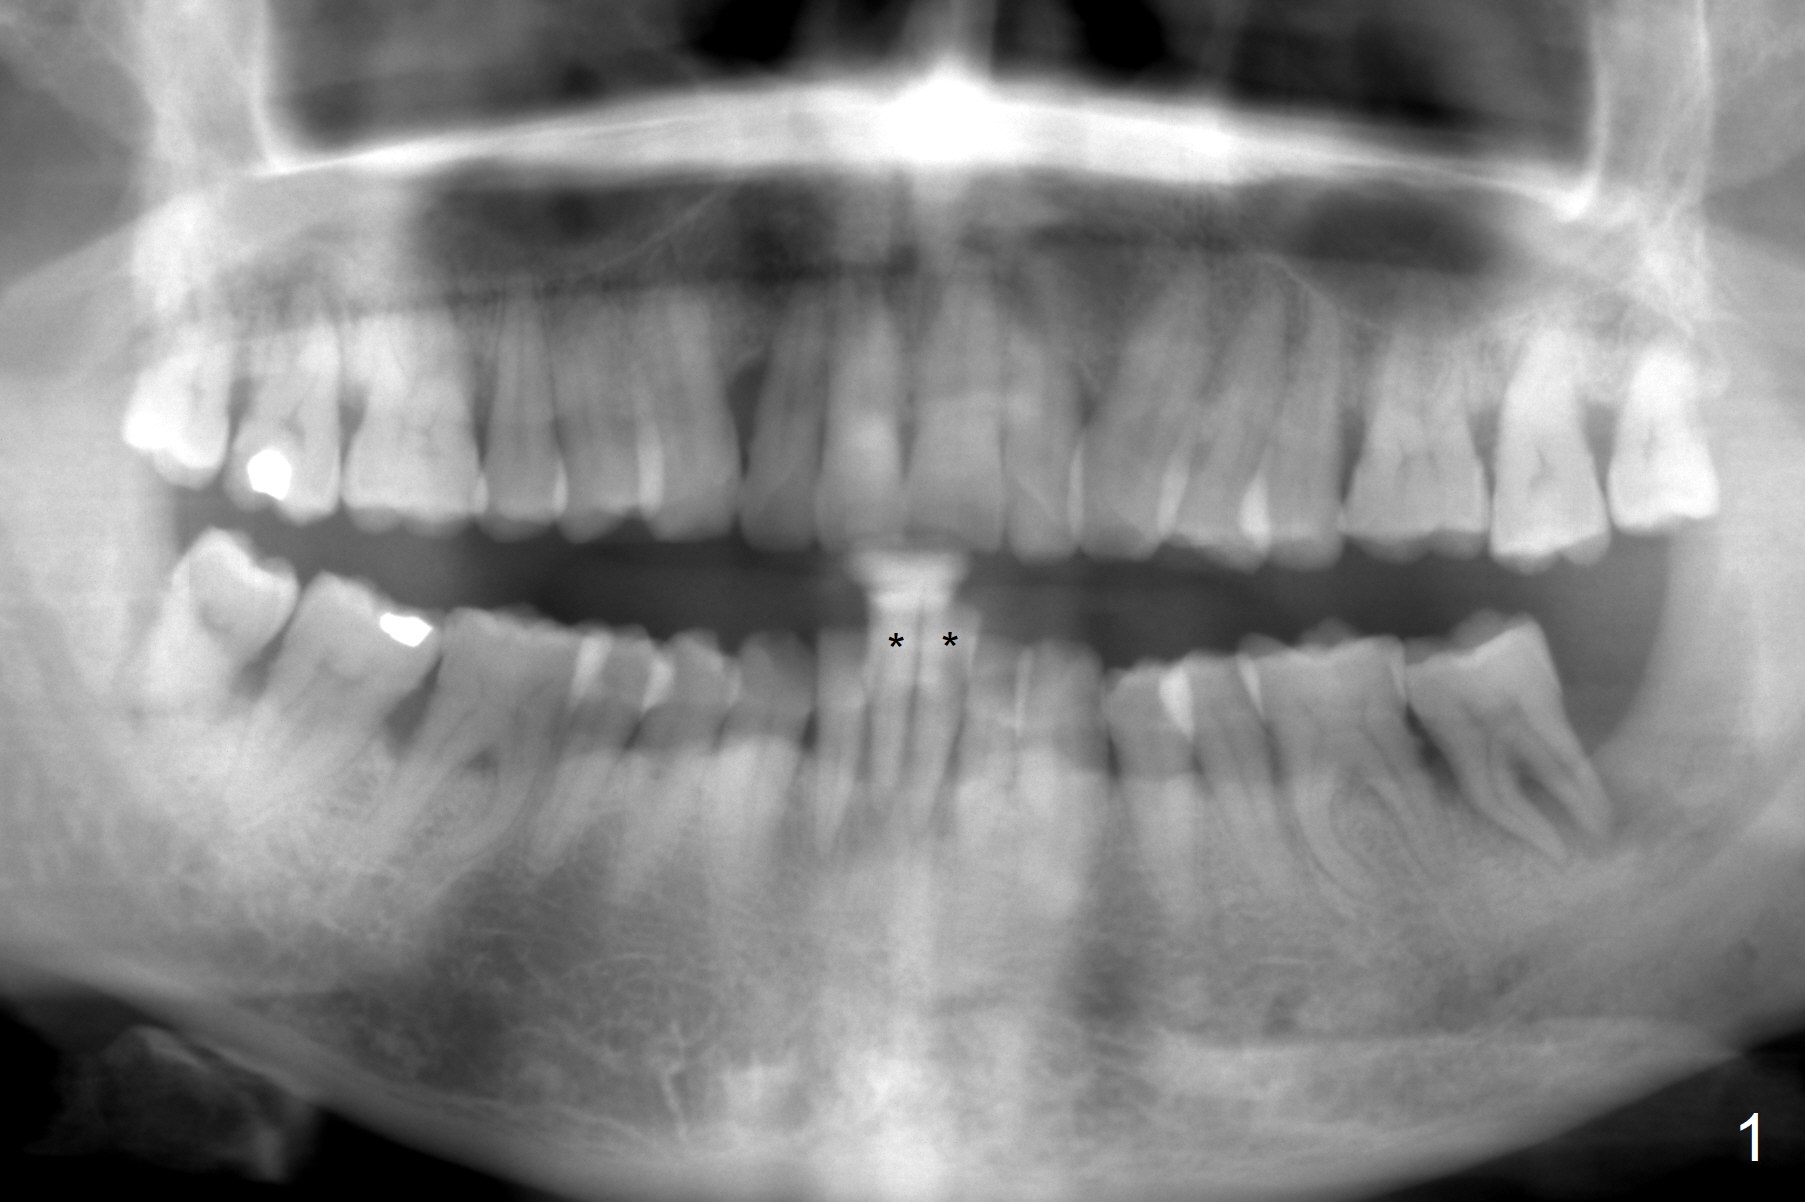

Two Lower Incisors, One Implants, Two Crowns

A 59-year-old man has two mobile central incisors, which are lingually displaced (Fig.1 *). Take photos and PA when the patients arrives for surgery. After extraction, choose the larger socket for osteotomy for 1-piece implant. In fact these two teeth have been exfoliated by themselves. Use an upper central incisor crown form for provisional with a vertical slot buccally to mimic 2 lower fused incisors.